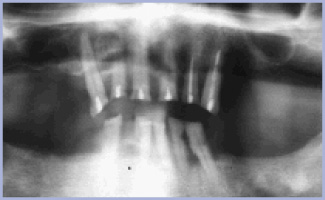

Paziente maschile di anni 66 non fumatore, con edentulia totale inferiore (figg. 1-2) ma nessuna notizia anamnestica particolarmente rilevante.

Si decide per l’inserimento di quattro impianti Ø 4,1 x 10 mm con tecnica chirurgica in due fasi (figg. 3-5).